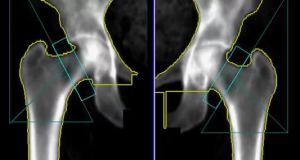

Если необходимо оценить проксимальный и дистальный механические углы, необходимо провести «слияние» двух рентгенограмм, при котором проксимальный и дистальный суставные концы будут находиться в состоянии правильной ортопедической проекции. Условная граница соединения рентгенограмм должна обеспечивать наиболее точное сопоставление кортикальных слоев кости из всех возможных вариантов как по ширине, так и относительно вертикальной оси кости с сохранением общей длины кости. На таком совмещенном изображении двух рентгеновских проекций можно одновременно достоверно оценить проксимальный и дистальный анатомические углы, а также проксимальный и дистальный механические углы.